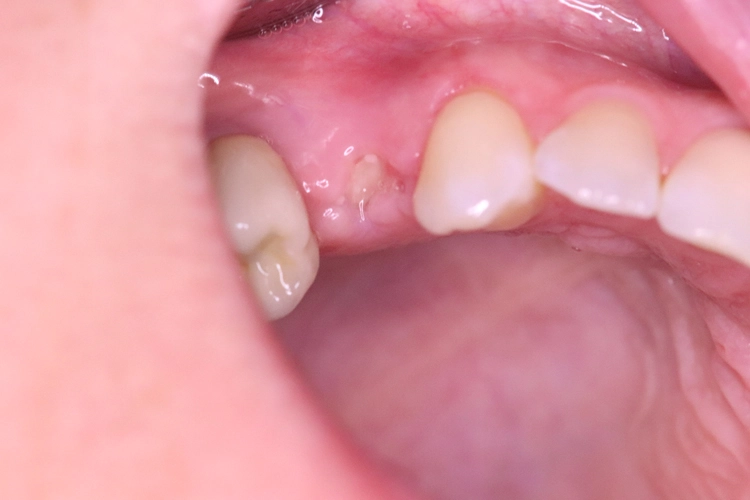

Aufgrund der traumatischen Extraktion des ankylosierten Zahnes, die zu einer Osteotomie wurde (Abb. 3), fehlten die vestibuläre und palatinale Lamelle (Röntgenkontrollbild während der Osteotomie, Wurzelrest noch vorhanden Abb. 4). Dieser Wurzelrest wurde entfernt. Bei dem geringen Restknochenvolumen war eine Sofortimplantation nicht mehr indiziert.

Der Erhalt der Weichgewebsstrukturen und des Kieferkamms wurde durch das Einbringen eines Knochenaufbaumaterials im Sinne einer Socket/Ridge Preservation ohne Membran gewährleistet (Abb. 5). Mesial zum 13 wurde eine resorbierbare Naht (SABAsorb rapid) gesetzt, um die Weichgewebe zu adaptieren. Die Kontrolle des Heilungsverlaufs nach dem Eingriff erfolgte ein Tag später (Abb. 6).

Kontrollbild und Röntgenkontrolle ein Jahr und ein Monat nach Socket/Ridge Preservation (Abb. 21 und 22). Der komplette Umbau zu Eigenknochen ist noch nicht abgeschlossen. Die Papillenregeneration zwischen 13/14 und 14/15 ist jedoch deutlich erkennbar.